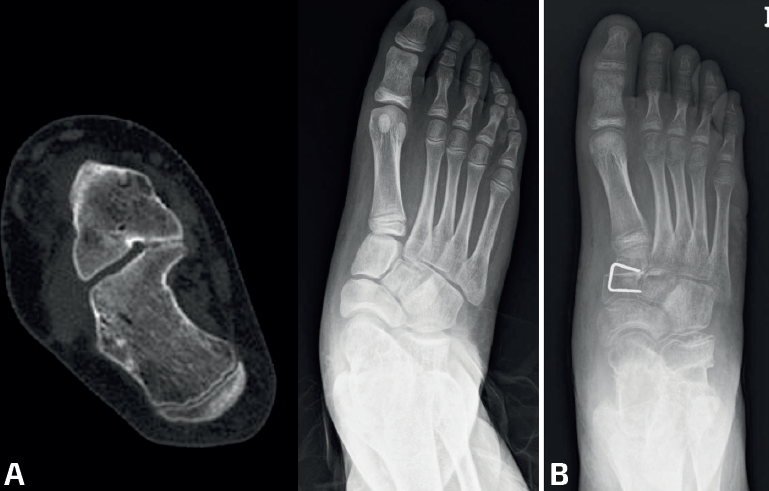

Cirugía de la coalición calcaneoescafoidea(10)

La resección suele ofrecer buenos resultados (78-90%), sobre todo en pacientes esqueléticamente inmaduros(9). Las coaliciones óseas tienden a tener peores resultados que las fibrocartilaginosas. Según Mosca(10,11), las coaliciones se consideran resecables si son fibrocartilaginosas, mientras que las coaliciones óseas son consideras irresecables, aunque existe controversia. Por otro lado, hay que valorar si existe un pie plano valgo que sea la causa de dolor del pie. Teniendo esto en cuenta, se describen 3 posibilidades terapéuticas:

- Resección aislada de la coalición. Se indica en casos de dolor localizado en la coalición sin aumento del valgo del retropié. Se realiza a través de un abordaje de Ollier sobre la coalición, guiado por radioscopia, teniendo cuidado de no lesionar el nervio peroneo superficial, se separa el extensor digitorum brevis hacia distal y se accede a la coalición. Se resecan aproximadamente 10-15 mm entre los huesos, con la interposición de grasa para disminuir el riesgo de recidiva, aunque puede usarse también músculo o cera(12). La osteotomía del escafoides se realiza en línea con el cuello del astrágalo, mientras que la del calcáneo se realiza en línea con el cuboides, debiendo llegar hasta una profundidad de aproximadamente 25 mm, para resecar bien la zona plantar. Las técnicas de resección endoscópica están ganando popularidad, ofreciendo resultados similares a la cirugía abierta(13,14)(Figura 4).

- Resección de la coalición asociada a corrección del pie plano valgo(10,15). Indicada en casos de pie plano valgo grave. La mayoría de los autores recomiendan realizar la resección de la coalición y la corrección del pie plano (mediante alargamiento de la columna externa, osteotomía de deslizamiento del calcáneo, artrorrisis o técnica de calcáneo-stop) en la misma cirugía. Sin embargo, otros sugieren realizar ambas cirugías en tiempos separados (primero la resección de la coalición y segundo la cirugía correctora del pie), dado que las pautas postoperatorias son diferentes y porque algunos pacientes mejoran la sintomatología tras la resección sin necesidad de realizar la cirugía del pie plano.

Nuestras opciones terapéuticas en este tipo de coalición van a depender del grado de deformidad del pie; si no existe deformidad en valgo preferimos realizar la resección aislada de la coalición. En casos con valgo aumentado realizamos resección de la coalición asociada a osteotomía del calcáneo de tipo Mosca/Evans en el mismo acto quirúrgico. En edad pediátrica preferimos este tipo de osteotomía a la de deslizamiento del calcáneo, para evitar lesionar la fisis de crecimiento del calcáneo.

- Resección de la coalición asociada a corrección del pie plano valgo: indicada en casos de CA resecable y valgo del retropié mayor de 16°. La resección de la coalición no restaura la morfología del pie, incluso puede empeorar el valgo del retropié. Se emplean técnicas como el alargamiento de la columna externa u osteotomía de deslizamiento medial del calcáneo, mejorando de forma significativa la función, la sintomatología y las imágenes radiográficas del pie. Si tras la corrección del valgo se objetiva supinación del antepié se asocia una osteotomía de flexión plantar de la primera cuña (Figura 8). La mayoría de los autores realizan ambos procesos simultáneamente. Otros autores recomiendan realizar ambos procedimientos en dos tiempos quirúrgicos separados en el tiempo, por las mismas razones que se han comentado anteriormente. Al igual que en las coaliciones CE, si existe una deformidad en valgo aumentada, preferimos realizar la cirugía simultáneamente.